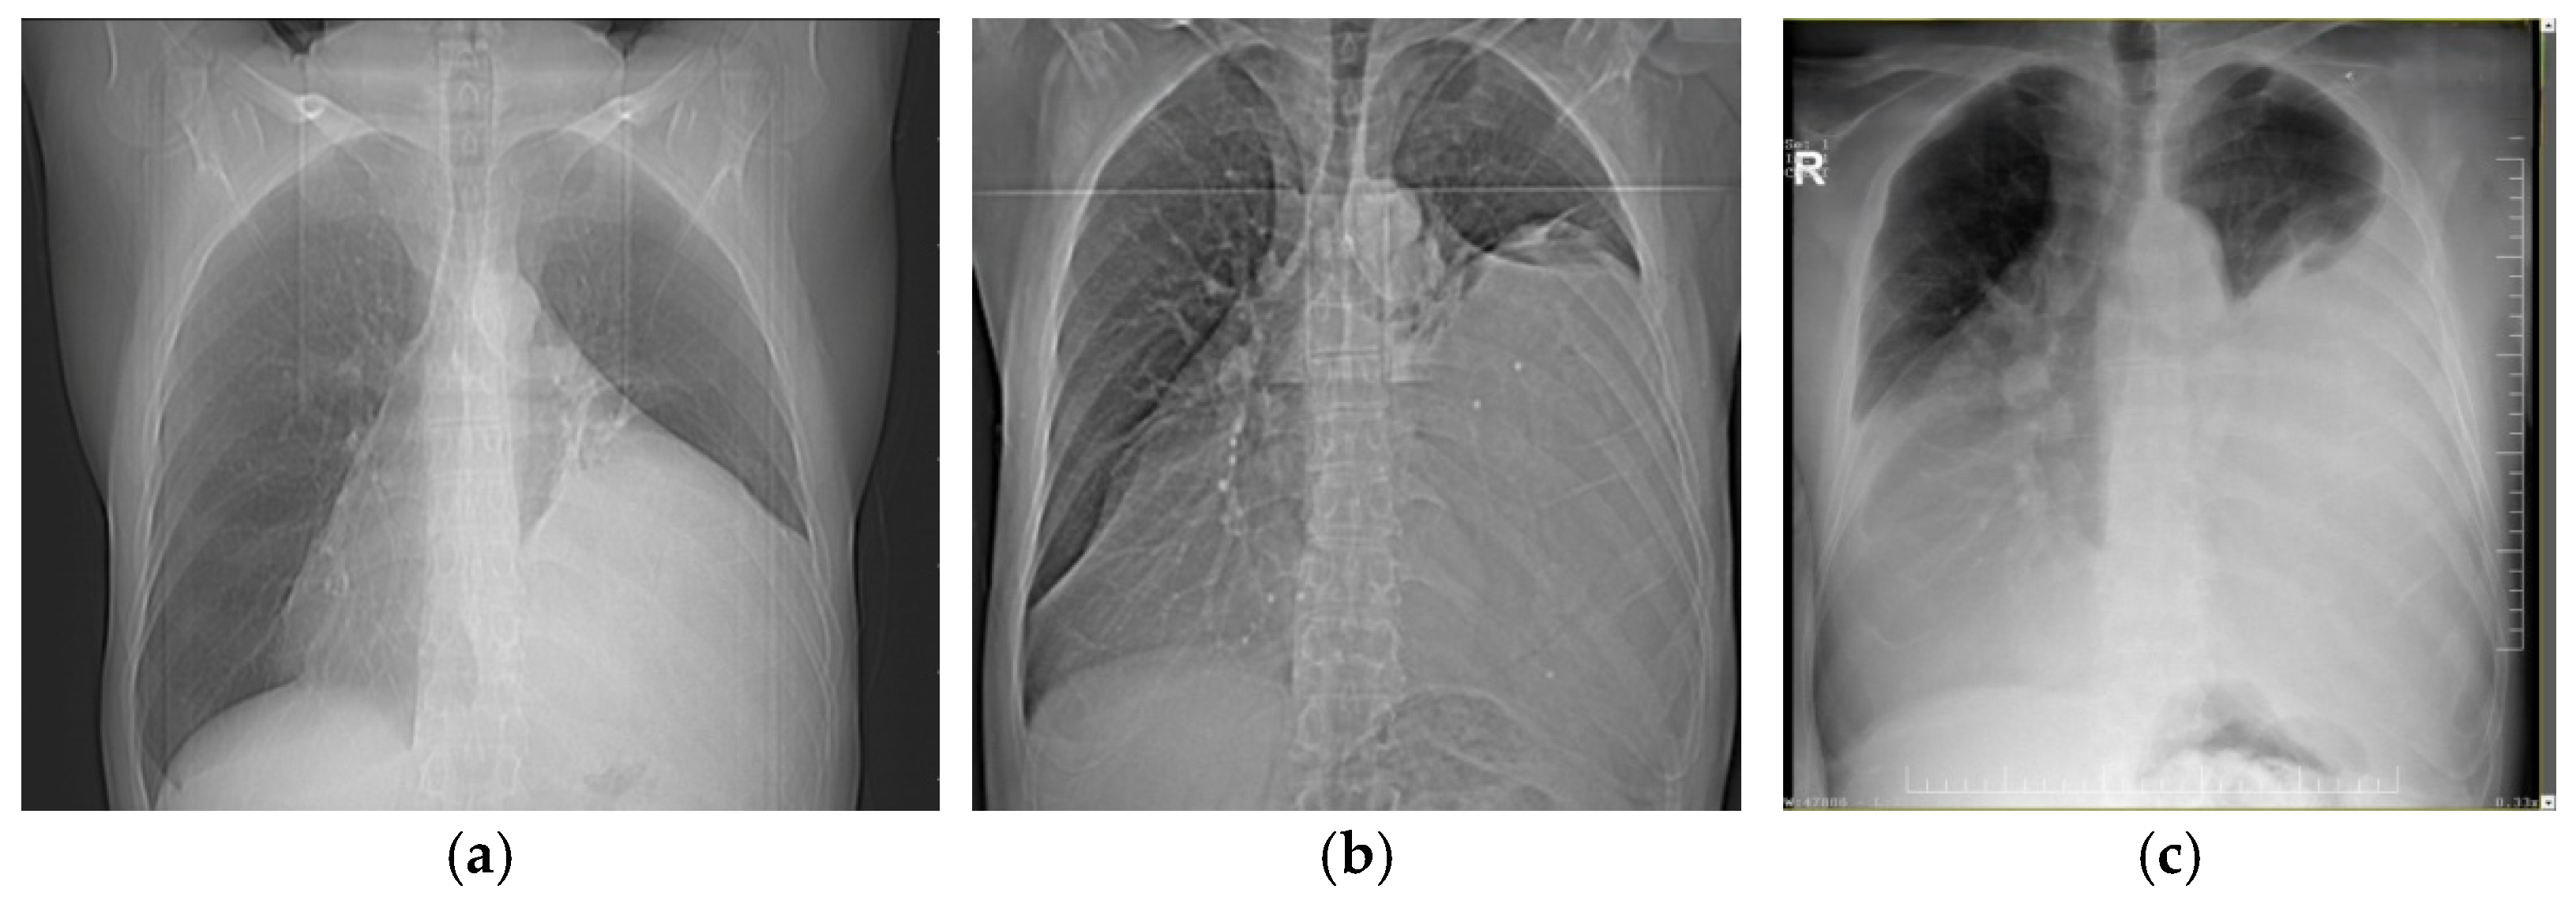

| CRC Stadium | Clinical-Radiological Findings |

| CRC 1 (minimal compression) |

|

| CRC 2 (moderate compression) |

| CRC 3 (“giant mediastinal tumor”) | |

| CRC 3A |

| CRC 3B |